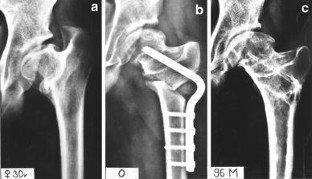

Fig. 1